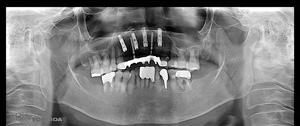

@@R.S‚³‚ñ@56Î —«  ‘åŠw‹³Žö @Žèp“ú@‚Q‚O‚O‚W”N ‚QŒŽ ‚X“úi“yj@㉺Š{  ƒm[ƒxƒ‹ƒKƒCƒhŽg—p@Ö¬“à’ÁÖ@•¹—p@@@

@@@@@ãŠ{  All on ‚U@‘¦Žž‰Ád@@

@@@@@@@@@@@@@ Rpl Tapered Rp  ‚P‚O mm(‚U–{)

@@@@@‰ºŠ{¶‰E@‘¦Žž‰Ád@ ‚R Unit Bridge@

@@@@@@@@@@@ @Rpl Tapered Rp  ‚P‚O mm(‚S–{)@@–ƒWƒ‹ƒRƒjƒAƒNƒ‰ƒEƒ“‚ÅÅI•â’Ô